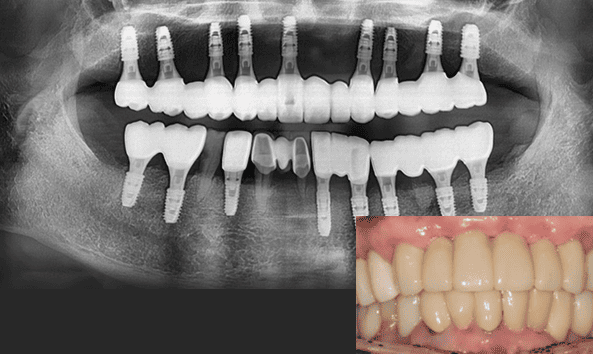

결과로 보여드리는 의료진의 노하우

- 24.07

* 임플란트 시술 시 교합이상, 신경손상, 염증 등의 부작용이 발생할 수 있습니다.

* 개인의 구강 및 치아상태에 따라 치료방법과 수가가 변동될 수 있습니다.

* 해당 사례는 의료법 제56조 2항을 준수하여 작성되었습니다.

* 본원에서 진료받은 환자이며 전후 사진의 인물이 동일인임을 밝힙니다.